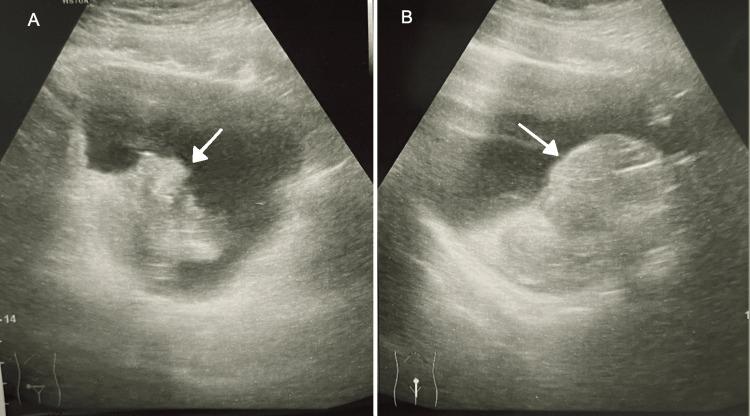

Inflammatory myofibroblastic tumour (IMT) of the urinary bladder is a rare mesenchymal neoplasm characterised by spindle-shaped myofibroblastic cells and an accompanying inflammatory infiltrate. Although its aetiology remains unclear, histopathological and immunohistochemical analyses are essential for diagnosis. We report the case of an 18-year-old male who presented with sudden-onset, painless gross haematuria. Initial evaluation revealed severe anaemia, necessitating blood transfusion. Renal ultrasound demonstrated a large echogenic lesion within the bladder. Cystoscopy revealed a large, polypoidal tumour on the right lateral bladder wall with active bleeding. The tumour was completely resected via transurethral resection of bladder tumour (TURBT). Histopathological examination confirmed IMT, with immunohistochemical staining positive for smooth muscle actin (SMA) and anaplastic lymphoma kinase (ALK), supporting the diagnosis. The patient remained stable postoperatively, with no recurrence at three- and six-month follow-up. Bladder IMTs are uncommon, particularly in young males, and typically present with non-specific urinary symptoms, most notably haematuria. Differentiation from other spindle cell neoplasms, including urothelial carcinoma and sarcomas, is crucial for appropriate management. Complete surgical excision is typically curative, and ongoing surveillance with periodic cystoscopy is recommended due to the potential for recurrence. IMT of the bladder is a rare but important differential diagnosis for bladder tumours in young patients presenting with haematuria. Timely diagnosis and surgical intervention can lead to favourable outcomes, underscoring the importance of clinical awareness.

膀胱炎性肌纤维母细胞瘤(IMT)是一种罕见的间叶性肿瘤,其特征为梭形肌纤维母细胞及伴随的炎性浸润。尽管其病因尚不清楚,但组织病理学和免疫组织化学分析对诊断至关重要。我们报告一例18岁男性患者,其表现为突发无痛肉眼血尿。初始评估显示严重贫血,需要输血。肾脏超声显示膀胱内有一个大的高回声病变。膀胱镜检查发现右侧膀胱壁有一个大的息肉样肿瘤并有活动性出血。通过经尿道膀胱肿瘤切除术(TURBT)将肿瘤完全切除。组织病理学检查确诊为IMT,免疫组织化学染色显示平滑肌肌动蛋白(SMA)和间变性淋巴瘤激酶(ALK)呈阳性,支持该诊断。患者术后情况稳定,在3个月和6个月随访时无复发。膀胱IMT并不常见,尤其是在年轻男性中,通常表现为非特异性泌尿系统症状,最显著的是血尿。与其他梭形细胞肿瘤,包括尿路上皮癌和肉瘤相鉴别,对恰当的治疗至关重要。完整的手术切除通常可治愈,鉴于有复发的可能,建议定期进行膀胱镜检查以持续监测。膀胱IMT是年轻血尿患者膀胱肿瘤的一种罕见但重要的鉴别诊断。及时诊断和手术干预可带来良好的结果,凸显了临床认识的重要性。